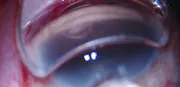

Bridging Gaps in Glaucoma Care With Supraciliary MIGS

Iqbal Ike K. Ahmed, MD, FRCSC; Arsham Sheybani, MD; and H. George Tanaka, MD